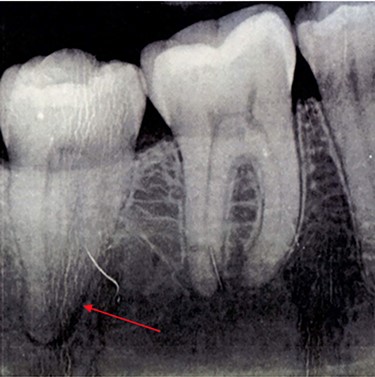

A 37-year-old fit and well lady presented to her General Dental Practitioner (GDP) complaining of pain in the right side of her mandible and episodic numbness in the ipsilateral mental nerve distribution. An orthopantomogram (OPG) (Fig. 1) was taken, with the GDP contentiously identifying an area of increased radiolucency at the apex of the right lower second molar. The patient was referred to a specialist dentist for root canal treatment of the tooth, with the GDP suspecting irreversible pulpitis.

OPG taken on patient’s first visit to GDP. Demonstrates radiolucency at apex of LR7.